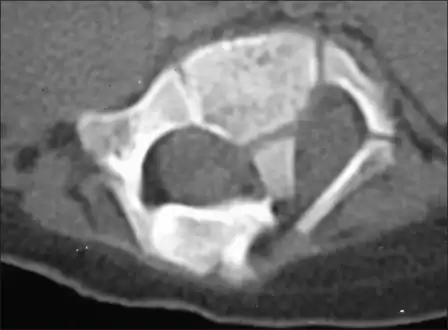

Diastematomyelia is a congenital disorder in which a part of the spinal cord is split, usually at the level of the upper lumbar vertebra in the longitudinal (sagittal) direction. This condition occurs in the presence of an osseous, cartilaginous or fibrous septum in the central portion of the spinal canal which then produces a complete or incomplete sagittal division of the spinal cord into two hemicords. When the split does not reunite distally to the spur, the condition is referred to as diplomyelia, which is true duplication of the spinal cord.

Diastematomyelia usually occurs between 9th thoracic and 1st sacral levels of the spinal column with most being at the level of the upper lumbar vertebra. Cervical diastematomyelia is a very rare entity. The extent (or length of spinal cord involved) varies from one affected individual to another. In approximately 60% of patients with diastematomyelia, the two hemicords, each covered by an intact layer of pia arachnoid, travel through a single subarachnoid space surrounded by a single dural sac. Each hemicord has its own anterior spinal artery. This form of diastematomyelia is not accompanied by any bony spur or fibrous band and is rarely symptomatic unless hydromyelia or tethering is present. The other 40% of patients have a bony spur or a fibrous band that passes through the two hemicords. In these cases, the dura and arachnoid are split into two separate dural and arachnoidal sacs, each surrounding the corresponding hemicord which are not necessarily symmetric. Each hemicord contains a central canal, one dorsal horn (giving rise to a dorsal nerve root), and one ventral horn (giving rise to a ventral nerve root.) One study showed the bony spur typically situated at the most inferior aspect of the dural cleft. They advised that if the imaging appears to show otherwise, a second spur (present in about 5% of patients with diastematomyelia) is likely to be present.

Adult presentation in diastematomyelia is unusual. With modern imaging techniques, various types of spinal dysraphism are being diagnosed in adults with increasing frequency. The commonest location of the lesion is at first to third lumbar vertebrae. Lumbosacral adult diastematomyelia is even rarer. Bony malformations and dysplasias are generally recognized on plain x-rays. MRI scanning is often the first choice of screening and diagnosis. MRI generally give adequate analysis of the spinal cord deformities although it has some limitations in giving detailed bone anatomy. Combined myelographic and post-myelographic CT scan is the most effective diagnostic tool in demonstrating the detailed bone, intradural and extradural pathological anatomy of the affected and adjacent spinal canal levels and of the bony spur.